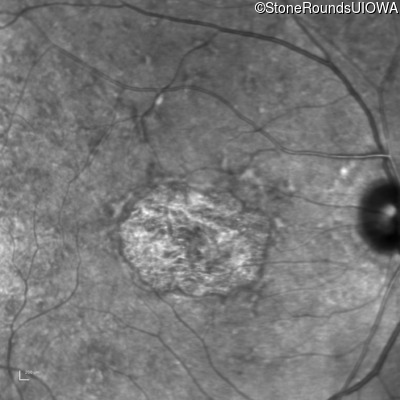

Pattern Dystrophy (IIC)

This 47 year man first experienced some decrease in his central vision about 10 years ago.

Diagnosis & molecular findings

Pattern Dystrophy PRPH2 Gly167Asp GGC>GAC   AD